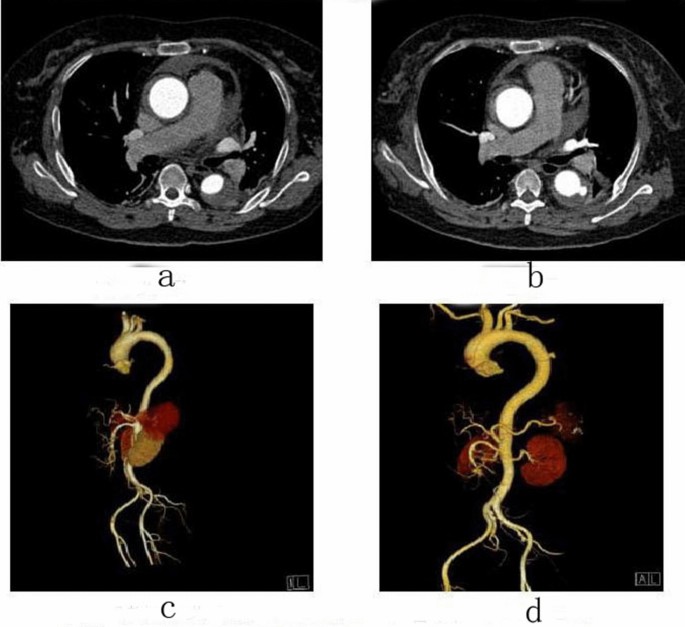

Follow-up

Female, 57 years old, admitted to hospital for “sudden pain in low back for 15 h”, Diagnosis: Stanford type A aortic dissection; treatment: IMH conservative treatment. CTA of the patient in different periods: (a) Admission; (b) 12 days after admission; (c) Admission; (d) 12 days after admission.